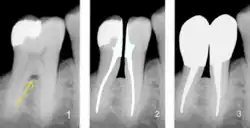

1) Freiliegende Bifurkation (Pfeil);

2) Prämolarisierung und Wurzelkanalbehandlung; 3) Zustand nach Überkronung mit Stiftaufbau; (Darstellung durch Bildbearbeitung);

Unter einer Hemisektion (von Altgriechisch: ήμἰ (hemi) (vergleiche:lat. semi) „halb“ und lat. sectio „das Zerschneiden“) versteht man in erster Linie die Durchtrennung eines unteren Molaren mit einer Teilextraktion einer Zahnwurzel. In sehr seltenen Fällen wird die Hemisektion auch an anderen mehrwurzligen Zähnen durchgeführt. Ein Sonderfall der Hemisektion wird als Prämolarisierung bezeichnet, bei der beide Wurzeln erhalten bleiben.

Prämolarisierung

Ein Sonderfall der Hemisektion wird als „Prämolarisierung“ bezeichnet (nicht zu verwechseln mit Prämolarisation). Dabei wird der Zahn nach durchgeführter Wurzelbehandlung ebenfalls durchtrennt, jedoch bleiben beide Wurzeln erhalten. Hierzu kommen in erster Linie die unteren Molaren in Frage. Damit wird eine freiliegende Bifurkation letztlich beseitigt, indem aus einem Molaren durch die Durchtrennung zwei Prämolaren, also zwei einwurzlige Backenzähne geschaffen werden. Diese sind nun besser zu reinigen und eine rezidivierende Entzündung wird durch die Auflösung der Bifurkation beseitigt. Der Therapieerfolg ist langfristig allerdings nur selten zufriedenstellend.[1]